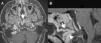

Clinical presentationA 16-year-old female with suspected diagnosis of recurrence of a clear cell meningioma (CCM) at a distance from the initial lesion, located on the premedullary cistern. The patient underwent a pure endoscopic low transclival approach. The attachment to the ventral surface of the brainstem was confirmed intraoperatively. Postoperative MRI confirmed gross total resection and treatment was complemented with adjuvant fractionated stereotactic radiotherapy. No complications related to the procedure were observed.

ConclusionMWODA may appear attached to the ventral brainstem. The expanded endonasal approach to the clivus provides a critical anatomical advantage in the treatment of medial lesions, even ventral meningiomas, to the lower cranial nerves. Reconstruction principles must be strictly respected to reduce complications.